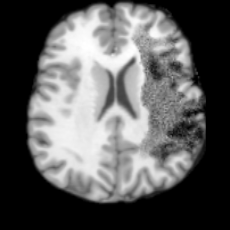

Pathology-to-Healthy Editing. Fig. 5 (a) presents comparison results on four input brain images with lesions of varying sizes, shapes, and densities. All competing models, although specialized for healthy brain image synthesis, struggle to reconstruct pathological regions, especially near lesion boundaries. In contrast, USB accurately reconstructs the corresponding healthy brain, even in challenging cases with large, high-density lesions where normal brain structures are almost completely obscured (last row). Tab. 2 provides a quantitative comparison for pathology-to-healthy editing, where USB achieves the best performance across all three datasets, demonstrating the effectiveness of its unified framework in reconstructing healthy brains from pathological inputs. Additional results are in Suppl. B.

Healthy-to-Pathology Editing. As shown in Fig. 5 (b), given a healthy brain image paired with a random lesion mask, USB seamlessly embeds the lesion into the healthy anatomy, producing realistic pathological appearances consistent with surrounding structural context. Yet UNA’s syntheses are visually unrealistic, with the conditioned lesion mask simply overlaid as a parallel layer onto the healthy brain. Tab. 3 further demonstrates USB’s superior performance. The evaluation was conducted on 100 pairs of lesion masks and healthy brains, with real stroke images